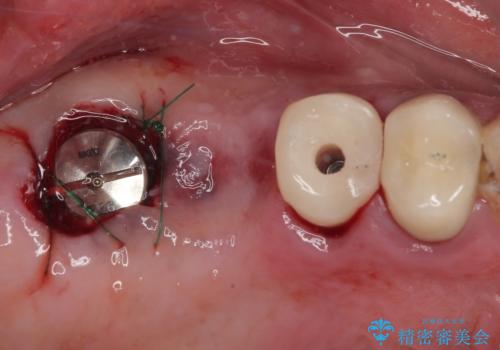

- 土台の歯が割れてしまって、歯がグラグラしているとのことで来院された患者様です。

いずれの歯も抜歯が必要な状態であり、抜歯即時埋入によるインプラント治療を行うこととしました。

右上奥歯は骨欠損の範囲が広いため、抜歯即時埋入は可能であっても、即日で仮歯を装着する即時荷重は難しいと判断されたため、手前の歯まで仮歯を装着することとしました。